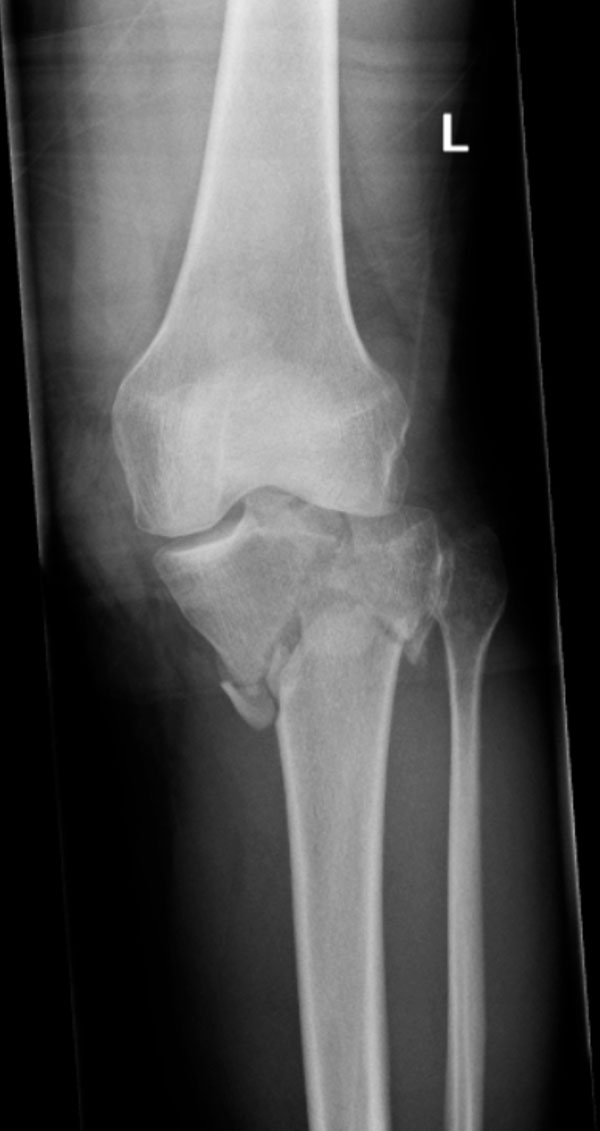

Fig. (1) Comminuted left tibial plateau fracture (Schatzker V) of patient A.